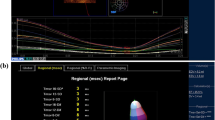

In addition to volumetric data, 2D measurements including tricuspid valve annulus (TVA) diameter, TAPSE, FAC, and free wall LS could be extracted from a non-shortened 4-chamber image derived from the same 3D dataset. Using STE, TAPSE was calculated as the difference in the distance between RV apex and the lateral aspect of the annulus at end diastole and systole. When measuring FAC, the trabeculations were included in the cavity of the RV in diastole. The free wall LS is an automated measurement as well. It was calculated as the difference in length of the line tracing the endocardial surface of the RV free wall from the apex to the lateral TV annulus in diastole (L0) and systole (L1) as per the following formula: LS = (L0 − L1/L0) * 100 (Fig. 4).

Non-foreshortened 2D images of the RV at end diastole and end systole. The free wall LS was calculated as the difference in length of the line tracing the endocardial surface of the RV free wall from the apex to the lateral TV annulus in diastole. LS longitudinal strain, RV right ventricle, TV tricuspid valve

From a non-foreshortened 4-chamber view of the RV generated from the 3D dataset, several 2D measurements were automatically presented by the software. The mean dimension of the tricuspid annulus was 11.1 ± 0.8 mm and lateral TAPSE measured was 6.8 ± 0.9 mm. In order to standardize the measured TAPSE, the value was divided by the length of the RV. The RV length was defined as the length of the line drawn from the point of intersection of the RV free wall and the interventricular septum to the midpoint of the line joining the TV hinge points at end diastole. The mean of indexed TAPSE (TAPSEi) was calculated at 24.2 ± 2.6%. The mean FAC was 43.9 ± 2.6%.

Right ventricular free wall LS was measured at (− 27.9 ± 2.5%). Conventional 2D echocardiographic parameters are presented in Table 2.